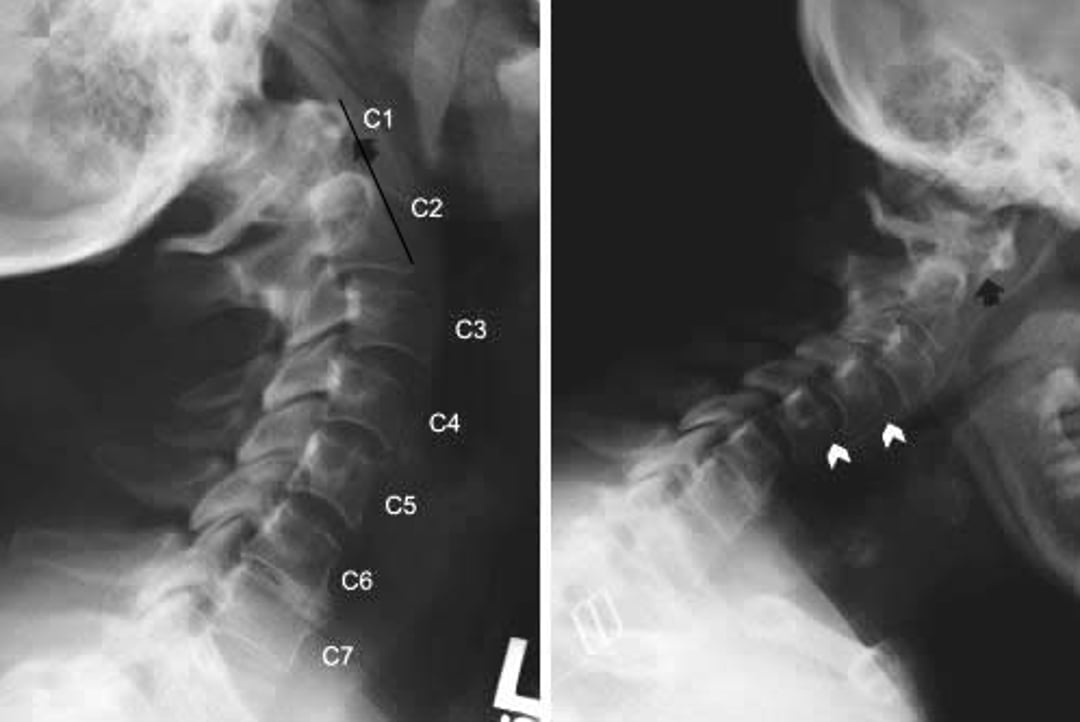

Subluxation axo-atloïdienne (atlantoaxoïdienne)

Rx du rachis cervical montrant une subluxation atlantoaxiale et une subluxation sous-axiale chez un patient atteint de polyarthrite rhumatoïde. Les incidences latérales du rachis cervical ont été prises en extension du cou (à gauche) et en flexion (à droite). En flexion, l'arc antérieur de C1 est très en avant de l'apophyse odontoïde de C2 (postérieure à la flèche noire), signe d'une subluxation antérieure. Ce signe n'est pas évident en extension (flèche noire), ce qui indique que la subluxation atlanto-axiale est dynamique. Un antérolisthésis (glissement vers l'avant du corps vertébral supérieur, indiqué par les pointes de flèches blanches) est également présent en C2-C3 et C3-C4 en extension et en C3-C4 et C4-C5 en flexion.